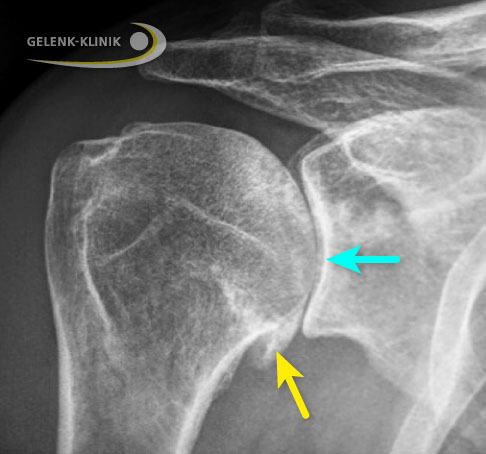

Bestehen Knochendefekte, wie sie bei einem langen Verlauf der Schulterarthrose vor allem im hinteren Bereich der Pfanne (Glenoid) auftreten können, ergänzt der Schulterspezialist die Diagnostik durch eine Computertomographie (CT). Die CT-Technik ermöglicht dem Arzt bei große Knochendefekten eine 3-D-Planung zur optimalen Vorbereitung, wenn er eine Operation in Betracht zieht.

Auf Röntgenaufnahmen erkennt der Schulterspezialist die typische Verschmälerung des Gelenkspalts bei Omarthrose. Die primäre Schulterarthrose zeigt in vielen Fällen eine Knorpelabnutzung der hinteren Anteile der Gelenkpfanne. Osteophyten sind Zeichen einer fortgeschrittenen Arthrose. Im späten Krankheitsstadium kann der Oberarmkopf ebenfalls verformt (deformiert) sein.